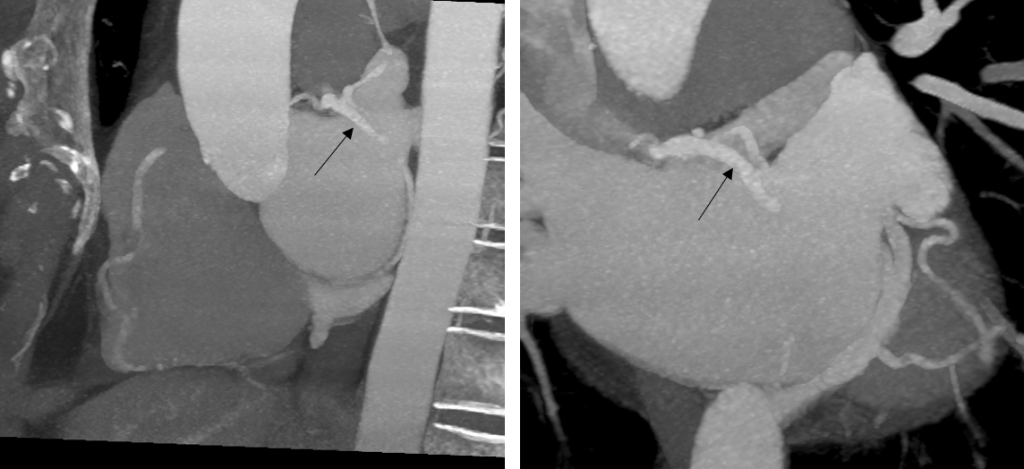

Figura 3: Fig 3 reconstrucţii oblic coronale MIP (maxim intensity projection) din achiziţie angioCT coronariană

Discuţie caz nr 50: Examinarea angioCT coronariană este actual indicație de clasa 1 la pacienții cu boală coronariană cronică; este cazul unui pacient care a fost diagnosticat la examinare angioCT cu fistulă între arteră coronară dreaptă și arteră pulmonară dreaptă.